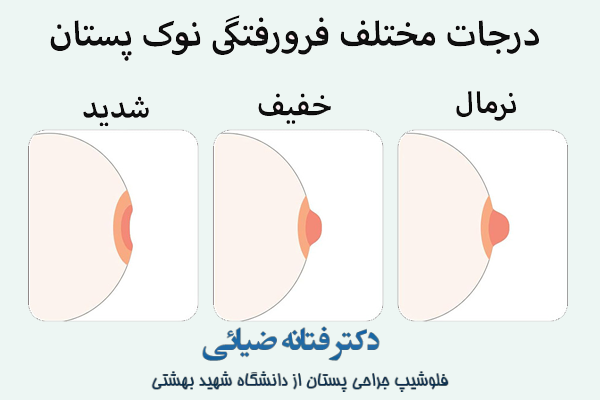

همانطور که اشاره شد، نوک پستان به دلایل گوناگون و با درجات مختلف ممکن است به مرور به داخل سینه متمایل شود. بر اساس همین تغییر شکل می توان سطح فرورفتگی را به سه دسته کلی تقسیم نمود:

- فرورفتگی خفیف که در این حالت می توان با لمس کردن نوک سینه را بیرون آورد.

- فرو رفتگی متوسط که در این حالت نیز به سختی می توان نوک سینه را بیرون آورده ولی دوباره به حالت قبلی خود باز می گردد.

- فرو رفتگی شدید که در این حالت اصلا نوک سینه قابل مشاهده و لمس فیزیکی نخواهد بود.